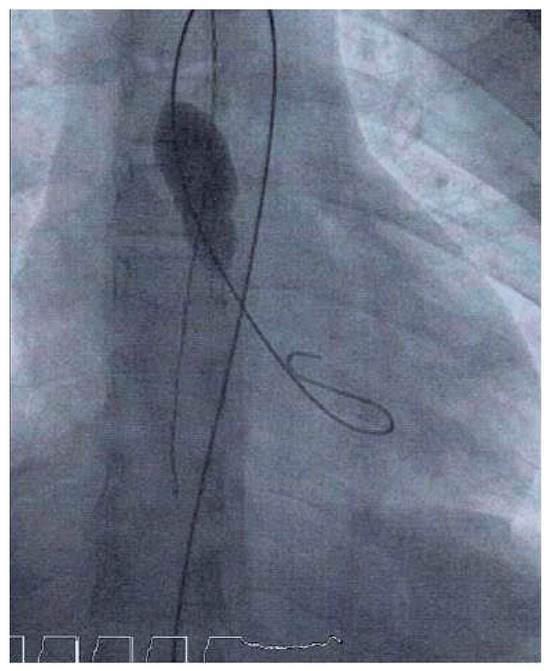

Prolonged Complete AV Block After Balloon Aortic Valvuloplasty in a Child

by Dina-Maria Jakob, Sabine Pallivathukal, Bernhard Meier and Jean-Pierre Pfammatter

Cardiovasc. Med. 2015, 18(10), 285; https://doi.org/10.4414/cvm.2015.00357 - 21 Oct 2015

A case is presented of prolonged complete atrioventricular block after elective balloon aortic valvuloplasty (BAV) of a congenital aortic stenosis in a 10-year-old patient. Implantation of a transient transvenous pacemaker for hemodynamic stabilization was required. Stable sinus rhythm reoccurred 72 hours after BAV. [...] Read more.

A case is presented of prolonged complete atrioventricular block after elective balloon aortic valvuloplasty (BAV) of a congenital aortic stenosis in a 10-year-old patient. Implantation of a transient transvenous pacemaker for hemodynamic stabilization was required. Stable sinus rhythm reoccurred 72 hours after BAV. Full article

Show Figures

Figure 1